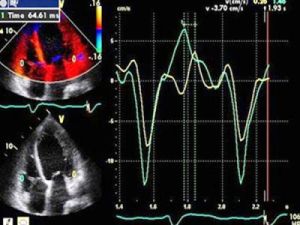

dti,全稱是doppler tissue imaging,都卜勒組織顯像,專業醫學英語簡寫。